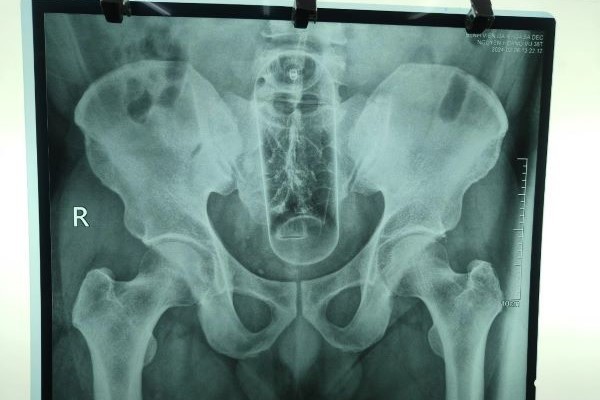

同省チャウタイン郡(huyen Chau Thanh)在住のVさん(36歳)は6日午前11時ごろ、排便しようとしたところ、でん部に激痛が走り、慌てて病院を訪れた。X線検査の結果、直腸に直径5cm・高さ20cm程のプラスチック製ボトルがあることが確認された。

医師らは患者に麻酔処置を施し、45分にわたる手術の末に直腸からボトルを摘出。術後の経過はよく、患者の容体も安定しており、数日後には退院できる見通しとのこと。